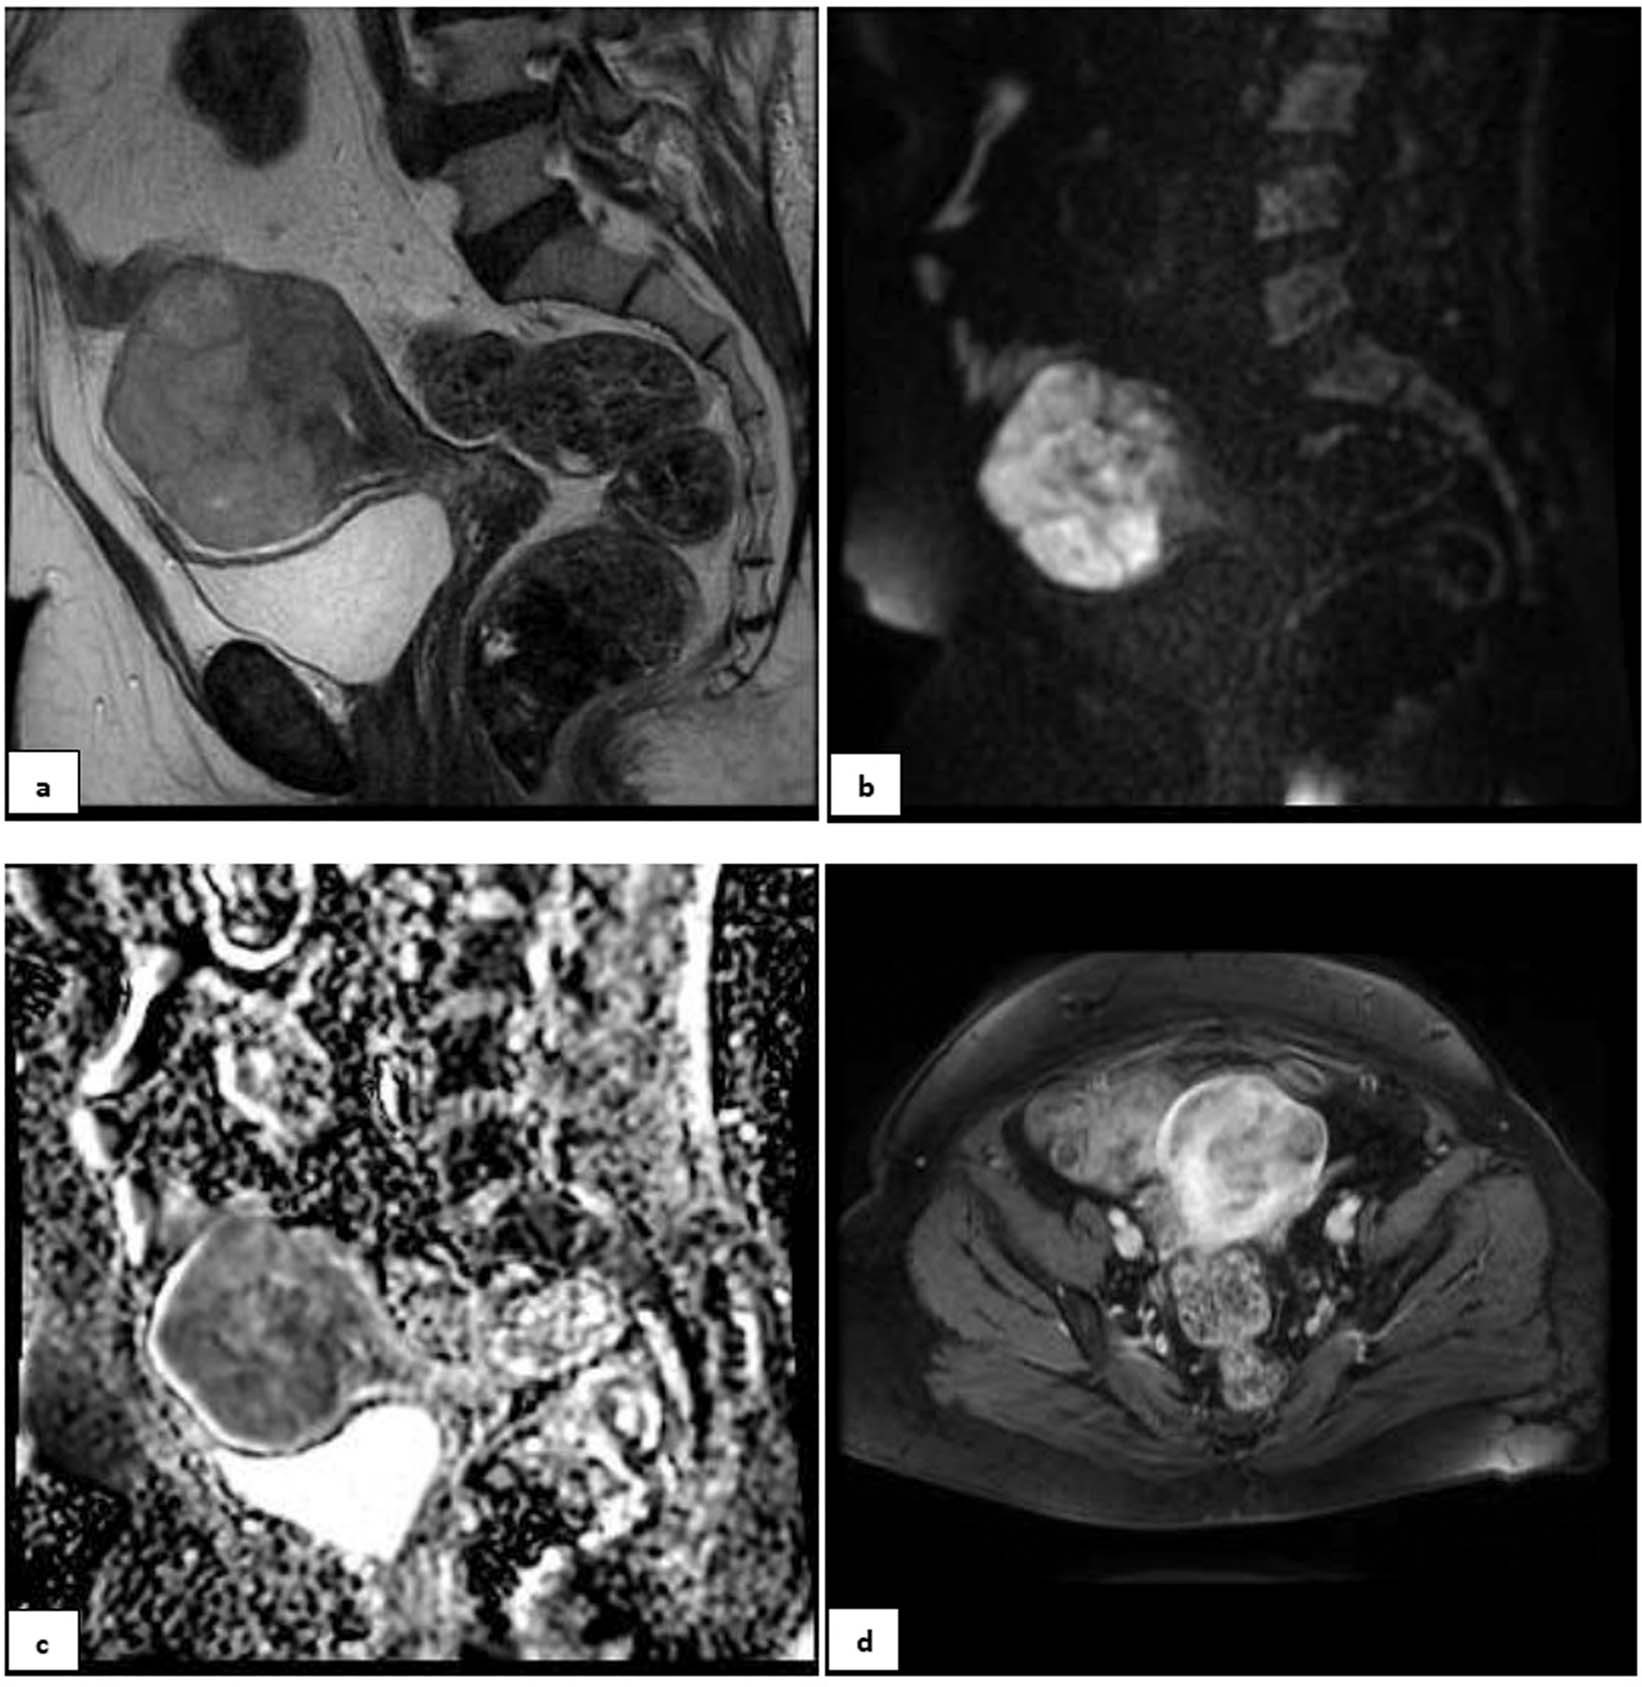

Figure 3

A 55-year-old postmenopausal patient with 3 months of abnormal uterine bleeding and a hypervascular myometrial mass on her ultrasound. (a) Sagital T2 MR-image detected a large predominantly hyper-signal lesion in anterofundal myometrium with extension to endometrial canal; Tumor-Myometrial Contrast (TM) Ratio = 1.98; T2-scaled Ratio = 1.01 and T2 map = 81. (b) Sagital-DW image and (c) ADC revealed restriction with mean ADC of 0.72 mm/s2. (d) Axial post contrast T1 image in equilibrium phase showed the mass has central necrosis and Tumor-Myometrium Contrast Enhanced (TMCE) Ratio = 1.1. If we put this sample data in either of simple or complex decision-tree, the pathology could be predicted as “malignant”. Eventually, the histo-pathological exam confirmed malignancy, a high grade sarcoma.